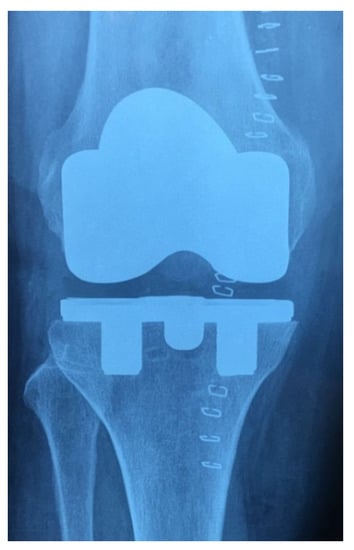

We retrospectively evaluated the records of patients who underwent primary TKA using a tantalum tibial component, totaling 52 consecutive patients between January 2017 and April 2018. Two groups were identified based on the different tibial component implanted. In 30 patients (Group A), a three-peg modular trabecular metal technology (TMT) component was implanted, and in 22 patients (Group B), a two-peg monoblock TMT component was chosen. The choice of implant depended on surgeon preferences. In Group A, the ultrahigh-molecular-weight polyethylene (UHMWPE) is mechanically locked into the tibial metal baseplate, and the inferior side of the baseplate reveals the presence of two hexagonal pegs that engage the area of highest tibial bone density (in line with the condylar loading), plus a central boss for the lock down screw (Figure 1). In Group B, there is a direct compression molding of the UHMWPE into the tibial metal baseplate, and the central boss is not present (Figure 2). The two cohorts were homogeneous in terms of diagnosis (all primary osteoarthritis), sex (all women), mean age, side of the involved knee, size of the tibial component, and thickness of the UHMWPE. Exclusion criteria were rheumatoid/inflammatory arthritis, TKA revision, post-traumatic arthritis, previous osteotomies, age > 80 years old, severe osteoporosis, and severe varus/valgus deformities (overall limb alignment more than 20°). The study protocol was in accordance with the Declaration of Helsinki for human research. Informed consent was obtained from all patients.

Figure 1. Three-peg modular TMT tibial component.